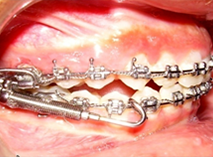

Tooth position can be corrected by Orthodontics, a branch of dentistry in which the teeth are moved into ideal and aesthetic positions using wires, elastics and brackets. The treatment is best done by a specialist who has completed a three years post graduate course in Orthodontics called an orthodontist.

Patient Undergoing Orthodontic Treatment